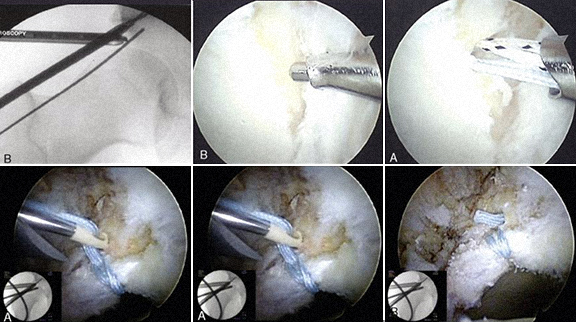

Deformidade óssea do rebordo acetabular (pincer)

Reparação e sutura de

lesão do labrum

Lesão da cartilagem articular, tratamento por desbridamento e microfracturas

Deformidade óssea do colo do fémur (CAM), resseção (femoroplastia)